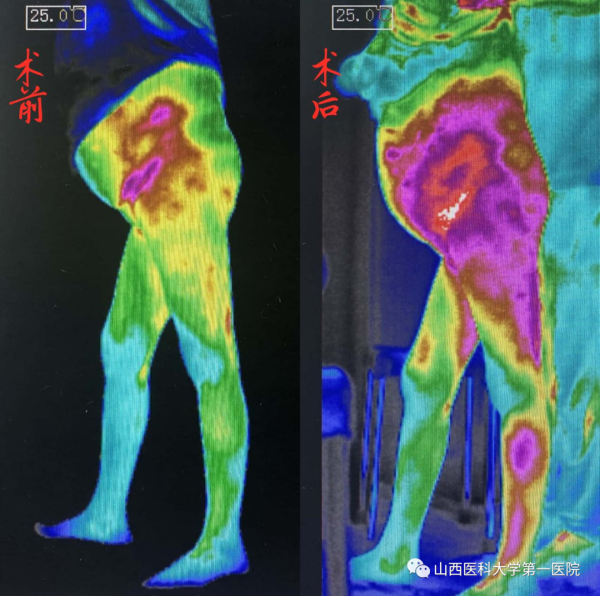

做完手术开机通电后,张老太感觉自己的双腿酥酥麻麻的,明显感到双下肢有一股暖流,脚一点都不疼了。开机当晚,张老太终于睡了一个久违的好觉。术后一个月,张老太复查情况良好,腿部色素沉着明显减轻,皮肤又恢复了光泽,右脚大拇指的溃疡已经痊愈,创伤的愈合对糖尿病患者来说比什么都可贵。红外热成像检查可以看到其下肢温度较术前明显改善,温度的提高反映了血液供应的恢复。张老太再也不用忍受下肢剧痛的折磨,终于可以下地走路了。